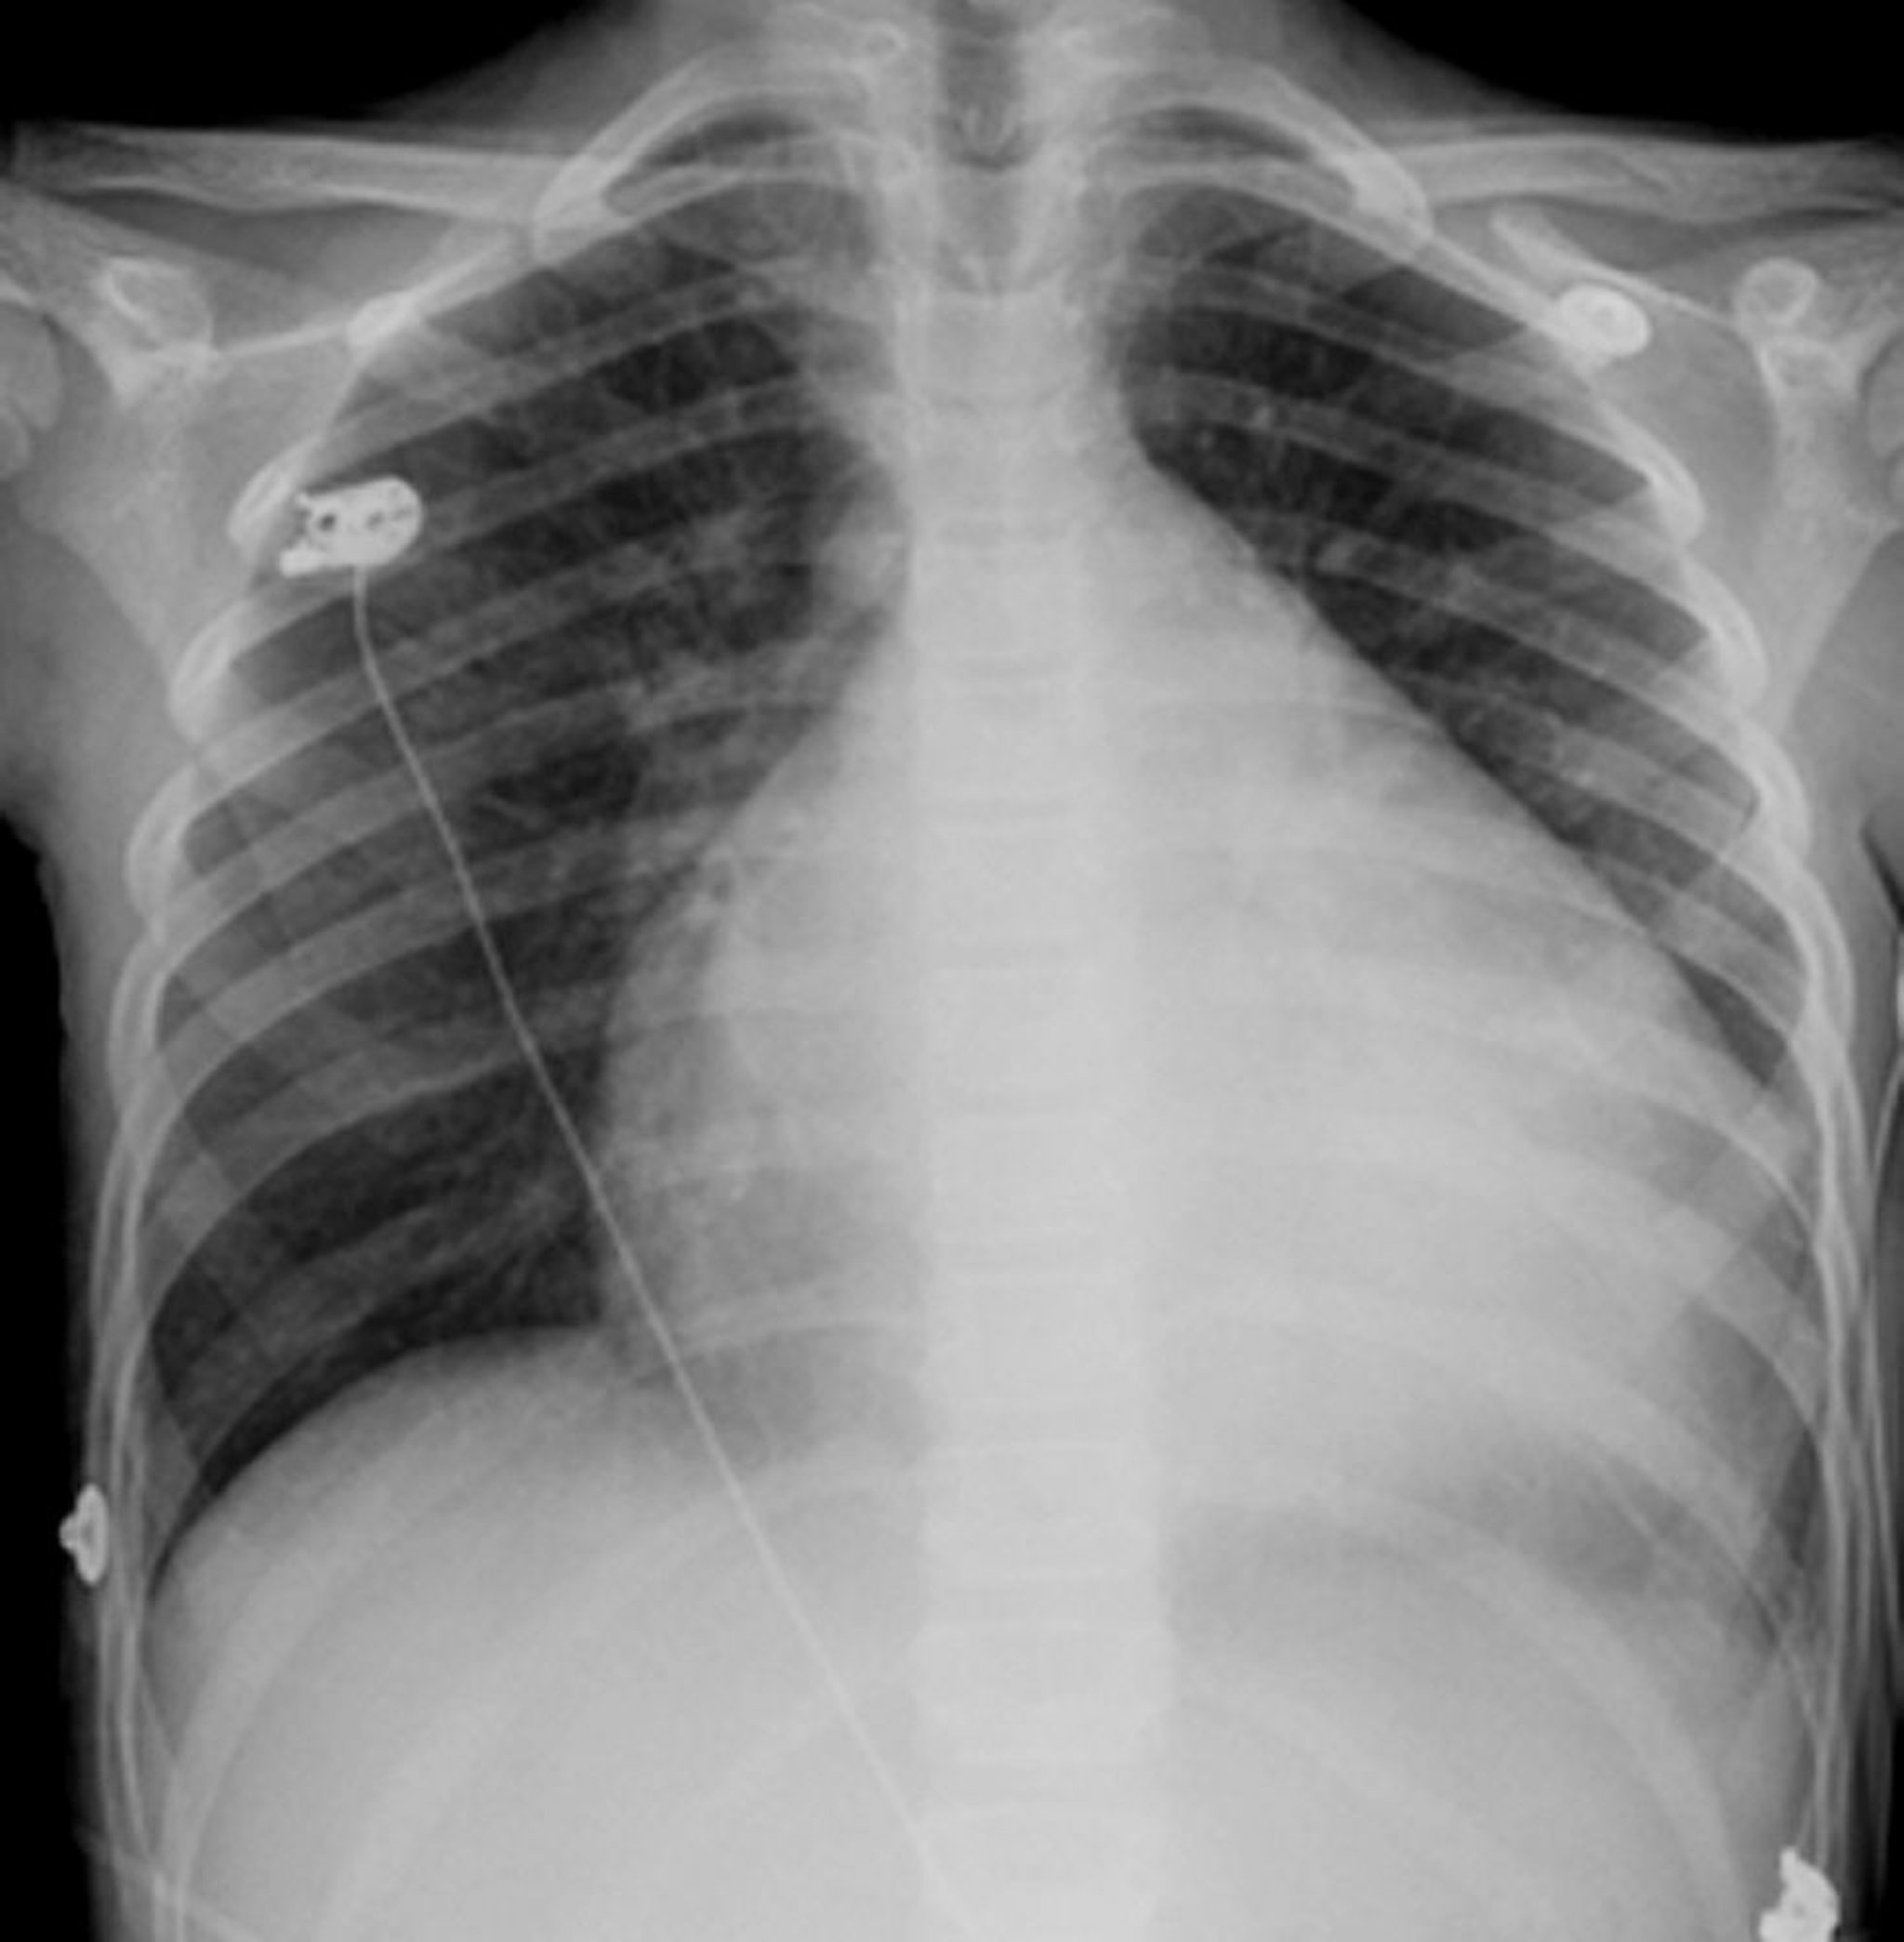

Il cuore è la struttura globulare e bianca al centro del torace. In genere occupa meno della metà della cavità toracica, ma in questo paziente con cuore ingrossato (cardiomiopatia), il cuore occupa quasi 3/4 della cavità toracica.